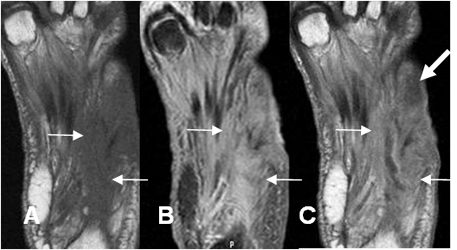

Fig 127 A. Osteomielitis.

A: Rx AP y B: Rx oblicua. Edema de tejidos blandos, con fístula cutánea en la parte externa. (Flechas delgadas). Ausencia del 5º metatarsiano y osteolisis del cuboides, la cuña lateral y las bases del 3º y 4º metatarsianos, por osteomielitis.

Fig 127 B. Osteomielitis.

A: RM coronal en T1, B: RM coronal en STIR y C: RM coronal en T1 con contraste. Igual paciente anterior. Cambios inflamatorios en los músculos y el tejido celular subcutáneo, sobre el medio pie. Los huesos cuboides, la cuña lateral y mitad inferior del 3º y 4º metatarsianos son hipointensos en T1, hiperintensos en STIR y realzan

con el contraste, por osteomielitis. Hay pequeña colección entre el 1º y 2º metatarsianos.